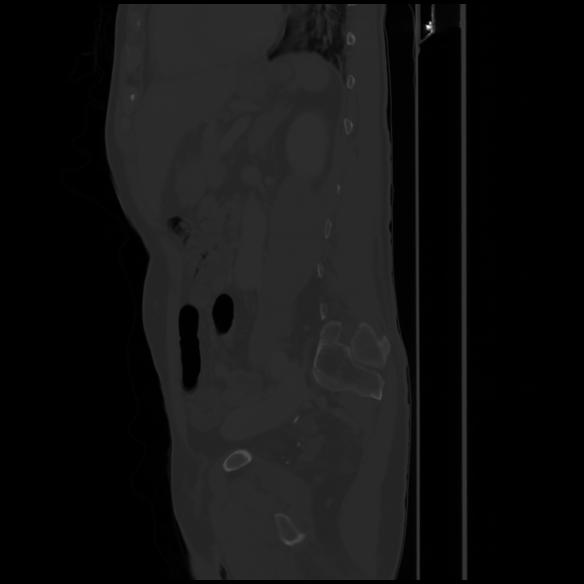

7 CUERPO,CE,Sagittal,3.000,CUERPO,Sagittal,